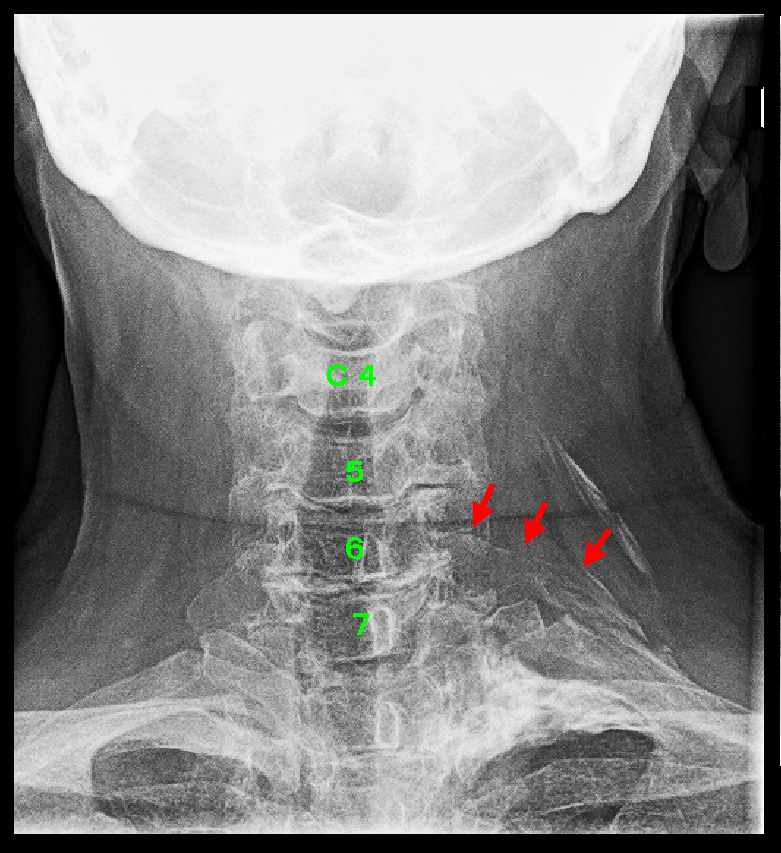

頚椎MRI検査では、(患者さんの首が短いためにきれいな画像となっていませんが)年齢相応の老化現象の所見ですが、C6-7での脊髄の圧迫が中等度~重度であり、これに起因する心臓近傍痛の可能性も推察されました。

C6-7に起因する症状であるのかどうかを明確にするために一番有効な対応はC6-7レベルでの神経根ブロックという治療です。ブロックで心臓近傍痛が軽減すれば、心臓近傍痛は頚椎C6-7の脊髄圧迫に起因していると判断することが可能です。患者さんはブロックを希望されたために、同日左C7神経根ブロックを施行しています。